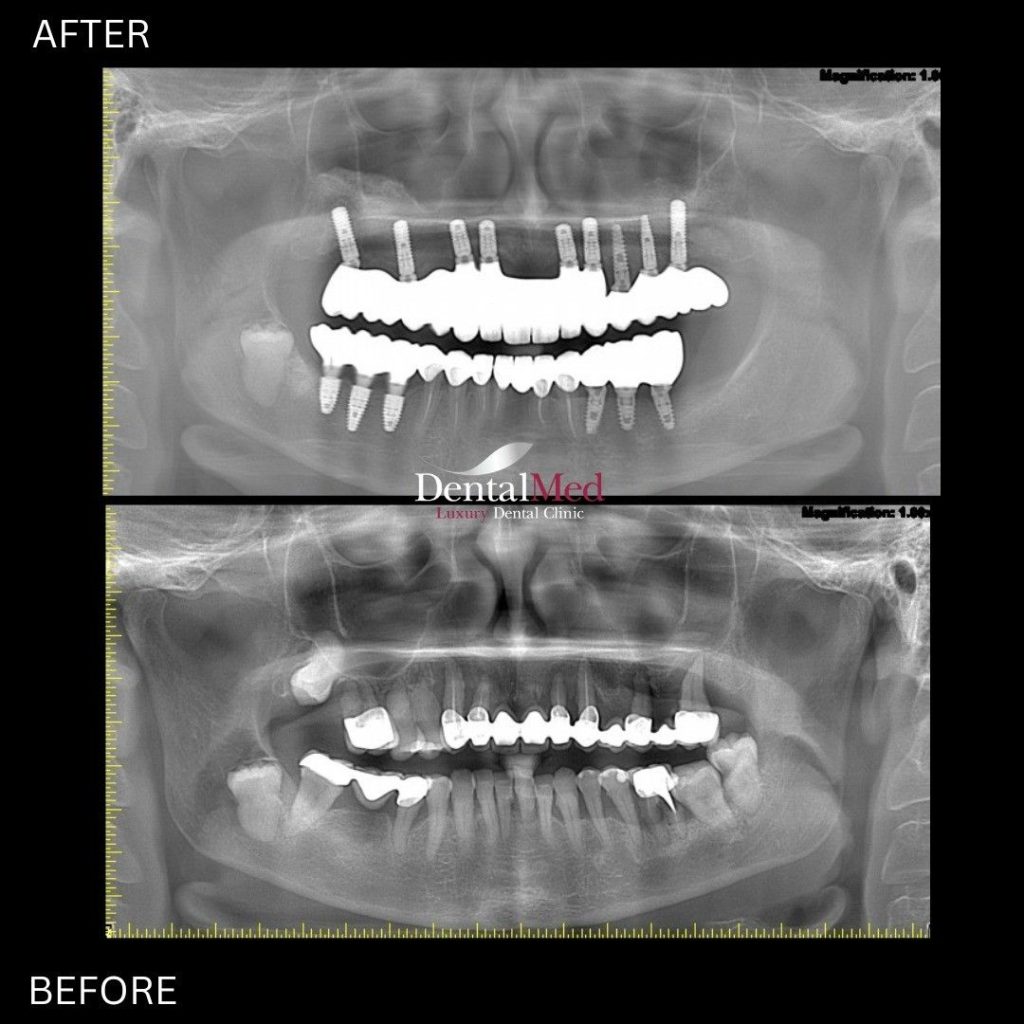

Membrana PRF are o utilizare extrem de variata in stomatologie. Ea este folosita cu succes nu doar in tratamentele cu implant dentar, ci si in:

Datorita proprietatilor sale biologice, membrana PRF contribuie la o vindecare mai rapida, o integrare mai buna a implantului dentar si la reducerea semnificativa a riscului de infectii.